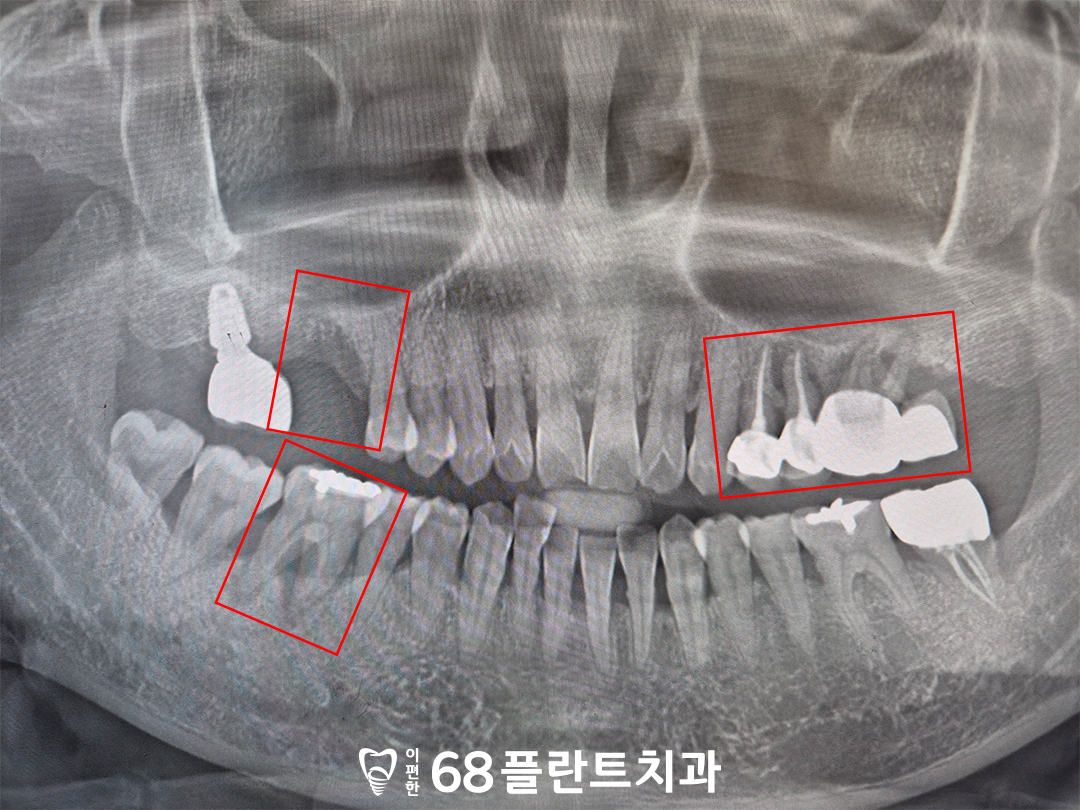

파노라마 사진을 촬영하여

확인해보니,

오른쪽 위 치아는

치아가 상실되었으며

왼쪽 위, 오른쪽 아래 어금니들이

잇몸병으로 인해

뼈가 많이 녹아있는 상황이었습니다.

육안으로도 잇몸의 부기가 뚜렷했고

전반적으로 치석이

많이 쌓여 있던 상황이었는데요.

이미 염증이 광범위하게 진행되었고

잇몸뼈의 흡수가 심해

기존 치아를 억지로 살리더라도

예후가 좋지 않을 것으로 판단되었습니다.